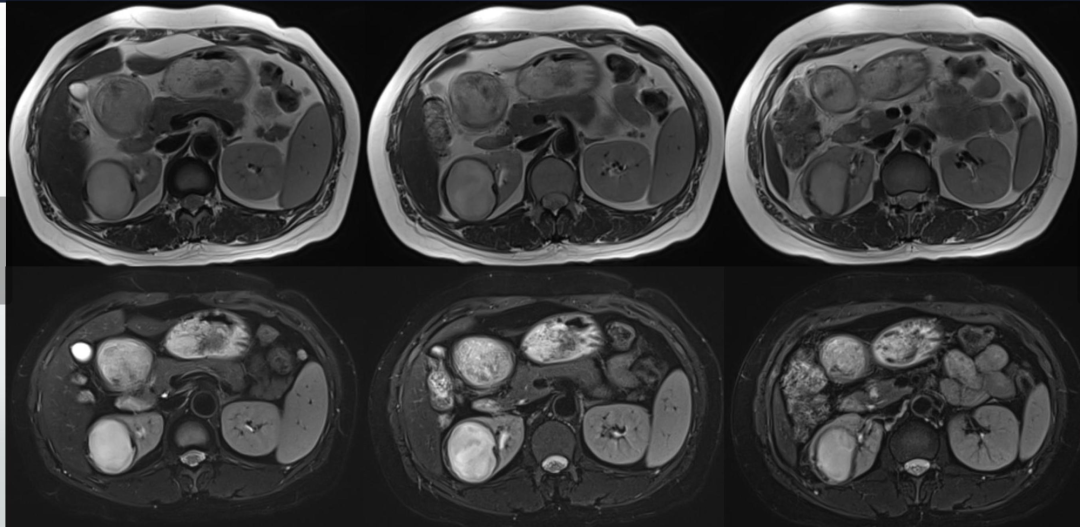

"熊掌征"表现为以肾盂肾盏为中心肾实质内多发囊性占位,其中部分囊为结石梗阻所致的肾积水,部分为黄色肉芽肿的脓腔;通常肾盏扩张为主,肾盂扩张常常不显,增强后,病变实性部分均匀强化,坏死区无强化,低密度区边缘环形强化。患肾体积增大或局限性隆起。常常伴有集合系统结石;肾皮质变薄;肾窦脂肪组织减少,多为慢性炎性反应性纤维组织增生所替代;肾周筋膜增厚、肾周间隙渗出积液,严重时可形成脓肿累及腰大肌。腹部X线平片典型的表现是受累的肾脏增大并有鹿角状结石,同侧腰大肌边缘模糊。超声显示肾脏轮廓变形,正常结构消失,中央可探及结石声影。

影像表现为:右肾囊性肿块,肾周无软组织及渗出影,增强囊壁轻度强化,囊内弥散受限明显,不强化,周围有出血